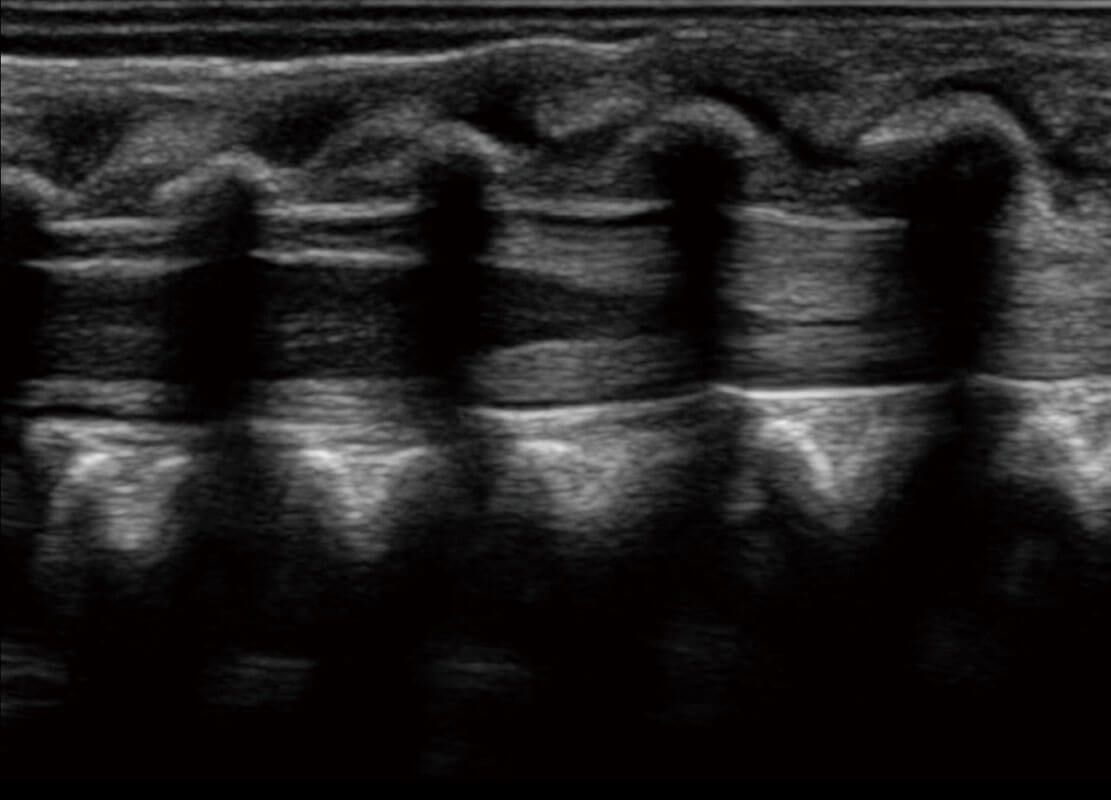

P60搭载一系列胎儿心脏成像技术,实现精细的胎儿心脏评估。

四腔切面